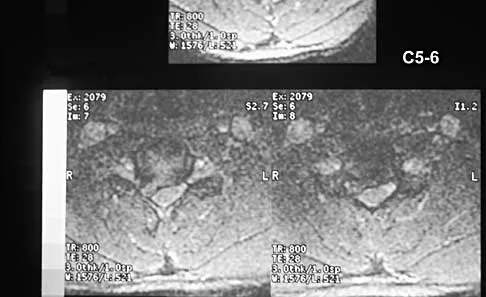

A 40-year-old carpenter has a 3-month history of right arm pain and neck pain that now leaves him unable to work. Examination reveals a positive Spurling test, weakness of the biceps, and a mildly positive Hoffman's sign on the right side. Electromyography and nerve conduction velocity studies show a right C6 deficit. Figures 27a through 27c show MRI scans that reveal two-level spondylotic disease at C5-6 and C6-7, a large herniated nucleus pulposus at C5-6, and a prominent ridge and hard disk at C6-7. Nonsurgical management fails to provide relief, so the patient elects surgical intervention. Which of the following surgical options would give the best long-term results?

The patient has a single-level deficit by clinical examination but an adjacent level that may be pathologic. Hilibrand and associates, in a review of 374 patients with myeloradiculopathy treated with single-level or multilevel anterior cervical diskectomy and fusion, showed that 25% of patients had an occurrence of new radiculopathy or myelopathy at an adjacent level within 10 years after surgery. Reoperation rates were highest in those patients where the adjacent nonfused segment was C5-6 or C6-7. Those patients who had multilevel fusions had a lower incidence of adjacent segment disease. The authors recommended incorporating an adjacent level in the initial procedure in patients with myelopathy or radiculopathy when significant disease was noted. Posterior keyhole foraminotomy is an excellent procedure for single-level radiculopathy but is not effective in relieving myelopathy. Anterior cervical diskectomy without fusion has an increased incidence of hypermobility and neck pain on long-term follow-up. In a later review, these authors reported improved fusion rates and better clinical outcomes with the use of strut fusions instead of multilevel interbody grafts. Hilibrand AS, Carlson GD, Palumbo MA, Jones PK, Bohlman HH: Radiculopathy and myelopathy at segments adjacent to the site of a previous anterior cervical arthrodesis. J Bone Joint Surg Am 1999;81:519-528. Henderson CM, Hennessy RG, Shuey HM Jr, Shackelford EG: Posterior-lateral foraminotomy as an exclusive operative technique for cervical radiculopathy: A review of 846 consecutively operated cases. Neurosurgery 1983;13:504-512.